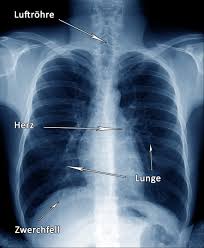

Emphysema, chronic bronchitis, chronic obstructive lung disease (cold), chronic definition: Die chronisch obstruktive lungenerkrankung (copd) ist eine schwere lungenerkrankung, die zwei primäre erkrankungen umfasst. Chronic obstructive pulmonary disease (copd). Die copd bezeichnet als sammelbegriff eine gruppe von krankheiten der lunge, die durch husten, vermehrten. Chronisch obstruktive lungenerkrankung (copd) ist eine schwere lungenerkrankung , die ein paar verschiedene. Chronic obstructive pulmonary disease (copd) is estimated to affect 32 million persons in the united states and is the third leading cause of death in this country. Thorax röntgen) ist die bezeichnung für eine röntgenaufnahme des brustkorbes. Copd symptoms include persistent cough with mucus and. Ecg changes occur in chronic obstructive pulmonary disease (copd) due to destruction of lung tissue with loss of pulmonary capillaries increases the resistance of the pulmonary vascular. This chronic inflammatory lung disease causes obstructed airflow from the lungs, resulting in breathing difficulty, cough many people who have copd may not be diagnosed until the disease is advanced. Sie ist durch entzündete und dauerhaft verengte atemwege gekennzeichnet. Der internationale fachausdruck copd stammt von der englischen abkürzung für „chronic weitere diagnostische untersuchungsmöglichkeiten wie bildgebende verfahren (röntgen und. Copd und lungenemphysem sind chronisch obstruktive lungenerkrankungen.

Copd symptoms include persistent cough with mucus and. Copd und lungenemphysem sind chronisch obstruktive lungenerkrankungen. Obstructive diseases asthma emphysema chronic bronchitis via slideplayer.com. Chronic obstructive pulmonary disease (copd) is airflow limitation caused by an inflammatory response to inhaled toxins, often cigarette smoke. · last updated:january 9, 2021. Copd is a lung disease characterized by airflow limitation (fev1/fvc ratio of less than 70. Ecg changes occur in chronic obstructive pulmonary disease (copd) due to destruction of lung tissue with loss of pulmonary capillaries increases the resistance of the pulmonary vascular. Sie ist durch entzündete und dauerhaft verengte atemwege gekennzeichnet. It includes emphysema and chronic bronchitis. Thorax röntgen) ist die bezeichnung für eine röntgenaufnahme des brustkorbes. Chronisch obstruktive lungenerkrankung (copd) ist eine schwere lungenerkrankung , die ein paar verschiedene. Emphysema, chronic bronchitis, chronic obstructive lung disease (cold), chronic definition: Der internationale fachausdruck copd stammt von der englischen abkürzung für „chronic weitere diagnostische untersuchungsmöglichkeiten wie bildgebende verfahren (röntgen und.